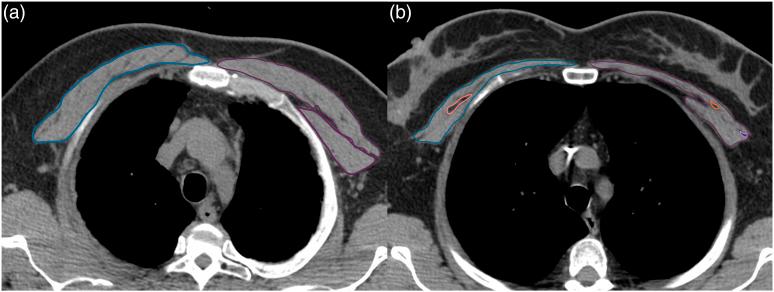

This cross-sectional study collected routine data from COVID-19 survivors one month after hospitalization: 1) a chest computed tomography (CT) scan and 2) a functional capacity test (30s-STS). The pectoralis muscle area (PMA) was measured from axial CT images. For each gender, patients were categorized into tertiles based on PMA. The 30s-STS was performed to determine the leg extension power. The allometric and relative STS power were calculated as absolute 30s-STS power normalized to height squared and body mass. The two-way ANOVA was used to compare the gender-stratified tertiles of 30s-STS power variants.

本横断面研究收集了 COVID-19 幸存者住院后一个月的常规数据:1)胸部计算机断层扫描(CT)扫描和 2)功能能力测试(30s-STS)。从轴向 CT 图像测量胸肌面积(PMA)。对于每个性别,根据 PMA 将患者分为三分位。30s-STS 用于确定腿部伸展力量。将绝对 30s-STS 功率归一化为身高平方和体重,计算出等比和相对 STS 功率。使用双因素方差分析比较 30s-STS 功率变量的性别分层三分位。